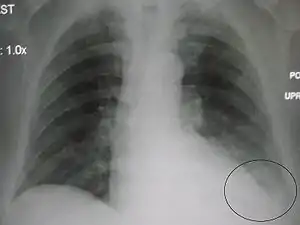

![]() Chest X-ray of a 30-year-old healthy man, with the costodiaphragmatic recess label in red ellipse | |

In anatomy, the costophrenic angles are the places where the diaphragm (-phrenic) meets the ribs (costo-).

Each costophrenic angle can normally be seen as on chest x-ray as a sharply-pointed, downward indentation (dark) between each hemi-diaphragm (white) and the adjacent chest wall (white). A small portion of each lung normally reaches into the costophrenic angle. The normal angle usually measures thirty degrees.

Pleural effusion

With pleural effusion, fluid often builds up in the costophrenic angle (due to gravity). This can push the lung upwards, resulting in "blunting" of the costophrenic angle. The posterior angle is the deepest. Obtuse angulation is sign of disease.

Chest x-ray is the first test done to confirm the presence of pleural fluid. The lateral upright chest x-ray should be examined when a pleural effusion is suspected. In an upright x-ray, 75 mL of fluid blunts the posterior costophrenic angle. Blunting of the lateral costophrenic angle usually requires about 175 mL but may take as much as 500 mL. Larger pleural effusions opacify portions of the hemithorax and may cause mediastinal shift; effusions > 4 L may cause complete opacification of the hemithorax and mediastinal shift to the contralateral side.